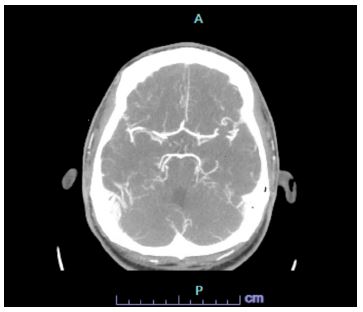

In the ED the patient denied any current symptoms and the physical exam was negative for any acute neurological findings with an NIHSS of 0. The patient’s parents at bedside endorsed dysarthria prior to arriving in the ED. A code stroke was initiated in the ED and a CT Head and CT angiogram were taken, both with unremarkable findings (Figures 1 & 2). Shortly after, the patient experienced another episode of dysarthria lasting for less than five minutes, to which a second code stroke was called and a perfusion CT was taken, showing increased Tmax in the left occipital lobe (Figure 3). Patient was transferred to the ICU for tenecteplase administration and observation with serial neurovascular checks and consults from neurology, cardiology, infectious disease.

Figure 2: CT angio.